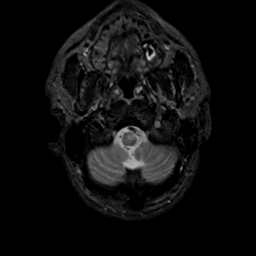

MR Study #17, July 7, 1991 -- Slice #4

[Home][Help][Clinical][Tour 1][Tour 2] Slice 4